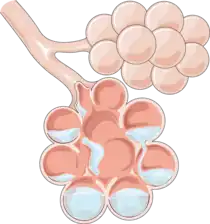

Pulmonary edema (British English: oedema), also known as pulmonary congestion, is excessive fluid accumulation in the tissue or air spaces (usually alveoli) of the lungs.[1] This leads to impaired gas exchange, most often leading to shortness of breath (dyspnea) which can progress to hypoxemia and respiratory failure. Pulmonary edema has multiple causes and is traditionally classified as cardiogenic (caused by the heart) or noncardiogenic (all other types not caused by the heart).[2][3]

Noncardiogenic pulmonary edema is caused by increased microvascular permeability (increased oncotic pressure) leading to increased fluid transfer into the alveolar spaces. The pulmonary artery wedge pressure is typically normal as opposed to cardiogenic pulmonary edema where the elevated pressure is causing the fluid transfer. There are multiple causes of noncardiogenic edema with multiple subtypes within each cause. Acute respiratory distress syndrome (ARDS) is a type of respiratory failure characterized by rapid onset of widespread inflammation in the lungs. Although ARDS can present with pulmonary edema (fluid accumulation), it is a distinct clinical syndrome that is not synonymous with pulmonary edema.